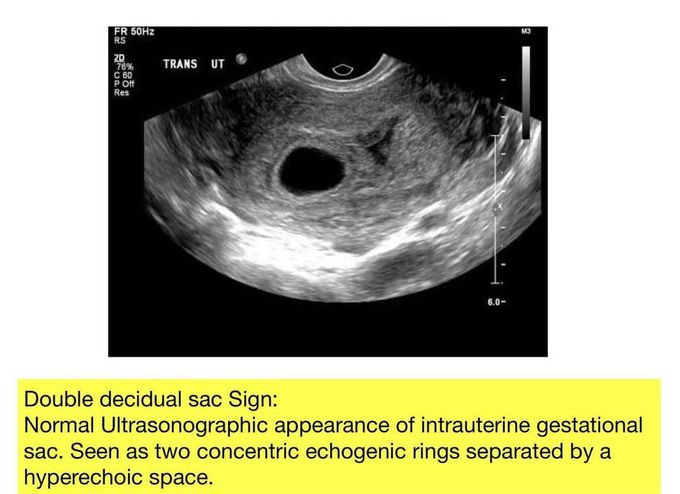

Double Decidual Sac Sign

Do you know what Double Decidual Sac Sign is?